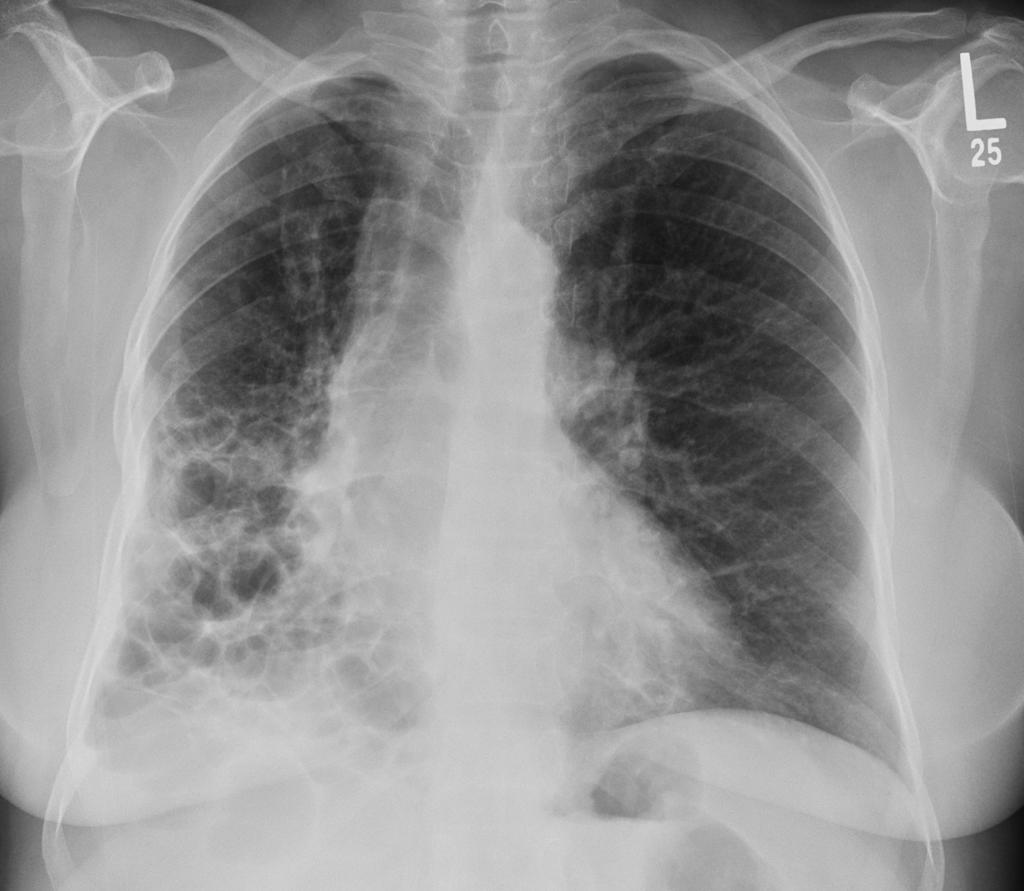

说起间质性肺疾病,很多朋友可能觉得陌生,但如果告诉你这是一种会让肺部逐渐变硬、呼吸越来越困难的疾病,你就知道它有多让人头疼了